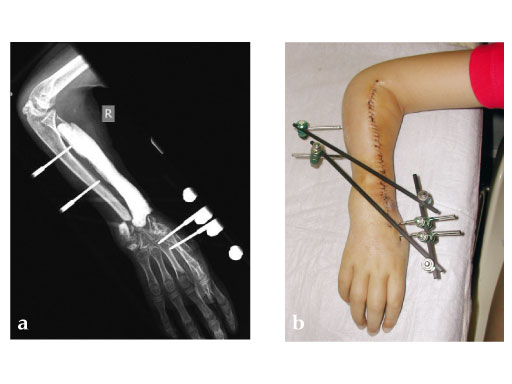

Fig 4ac: Postoperative.

Fig 5ab: Outcome after 2.5 months.